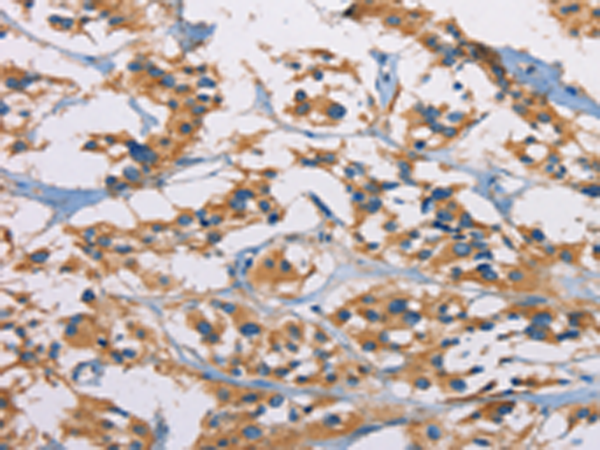

分类: 科研抗体货号: P08027别名: HNAC1; BCDase; LCDase; NCDase; N-CDase应用: WB,IHC反应种属: Human, Mouse, Rat